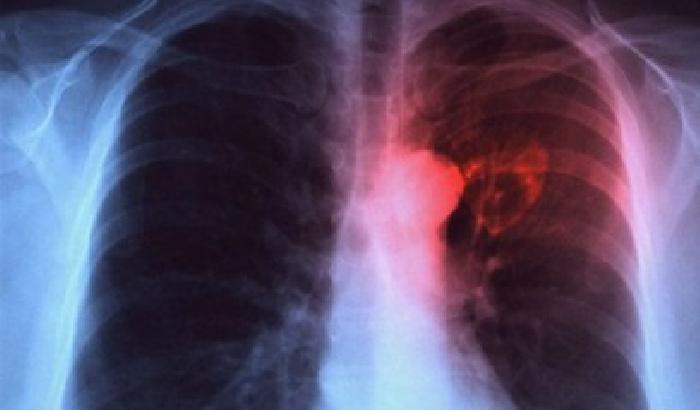

I risultati dello studio su questi apparecchio – sviluppato in collaborazione con l’Universita’ Tor Vergata di Roma – sono stati pubblicati sul Journal of Breath Research. Su un totale di 146 individui, di cui 70 con diagnosi di tumore e 76 senza segnali di malattia, l’apparecchio e’ stato in grado di discriminare il respiro di chi si stava ammalando di tumore polmonare rispetto a chi non correva alcun rischio, con una precisione del 90%.